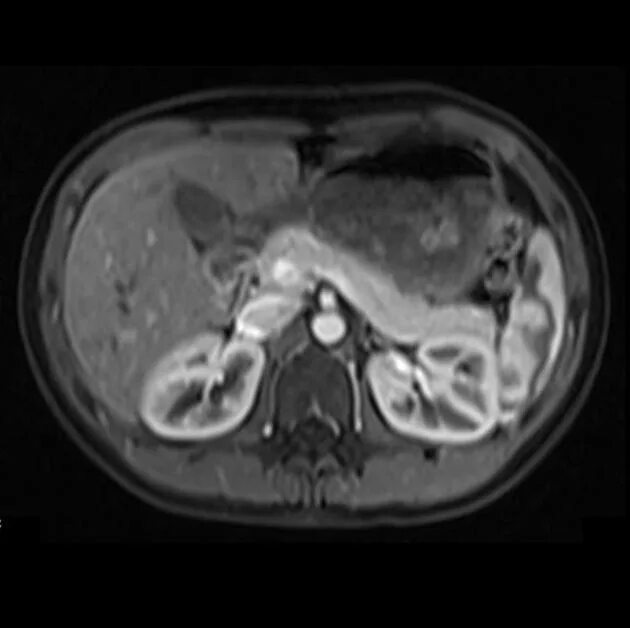

Что проверяет мрт брюшной полости